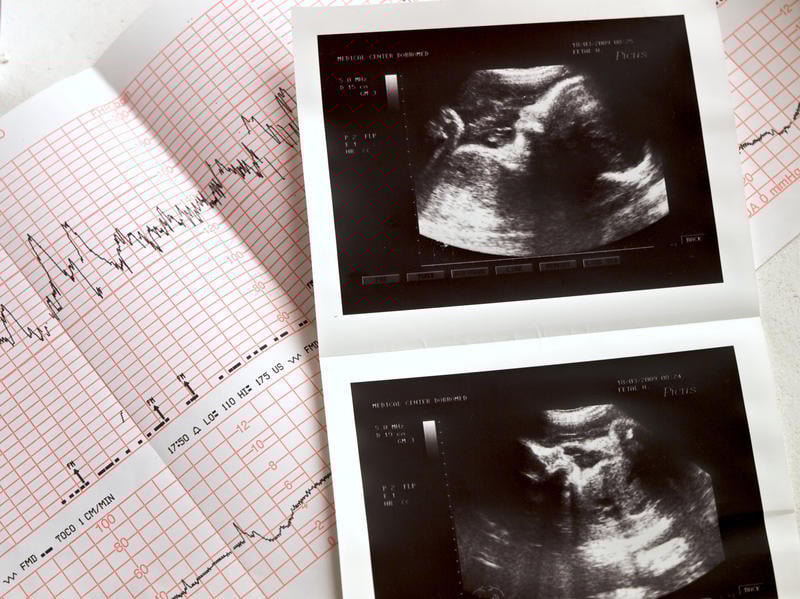

portrait échographique des résultats du fœtus et du cardiogramme

Istock